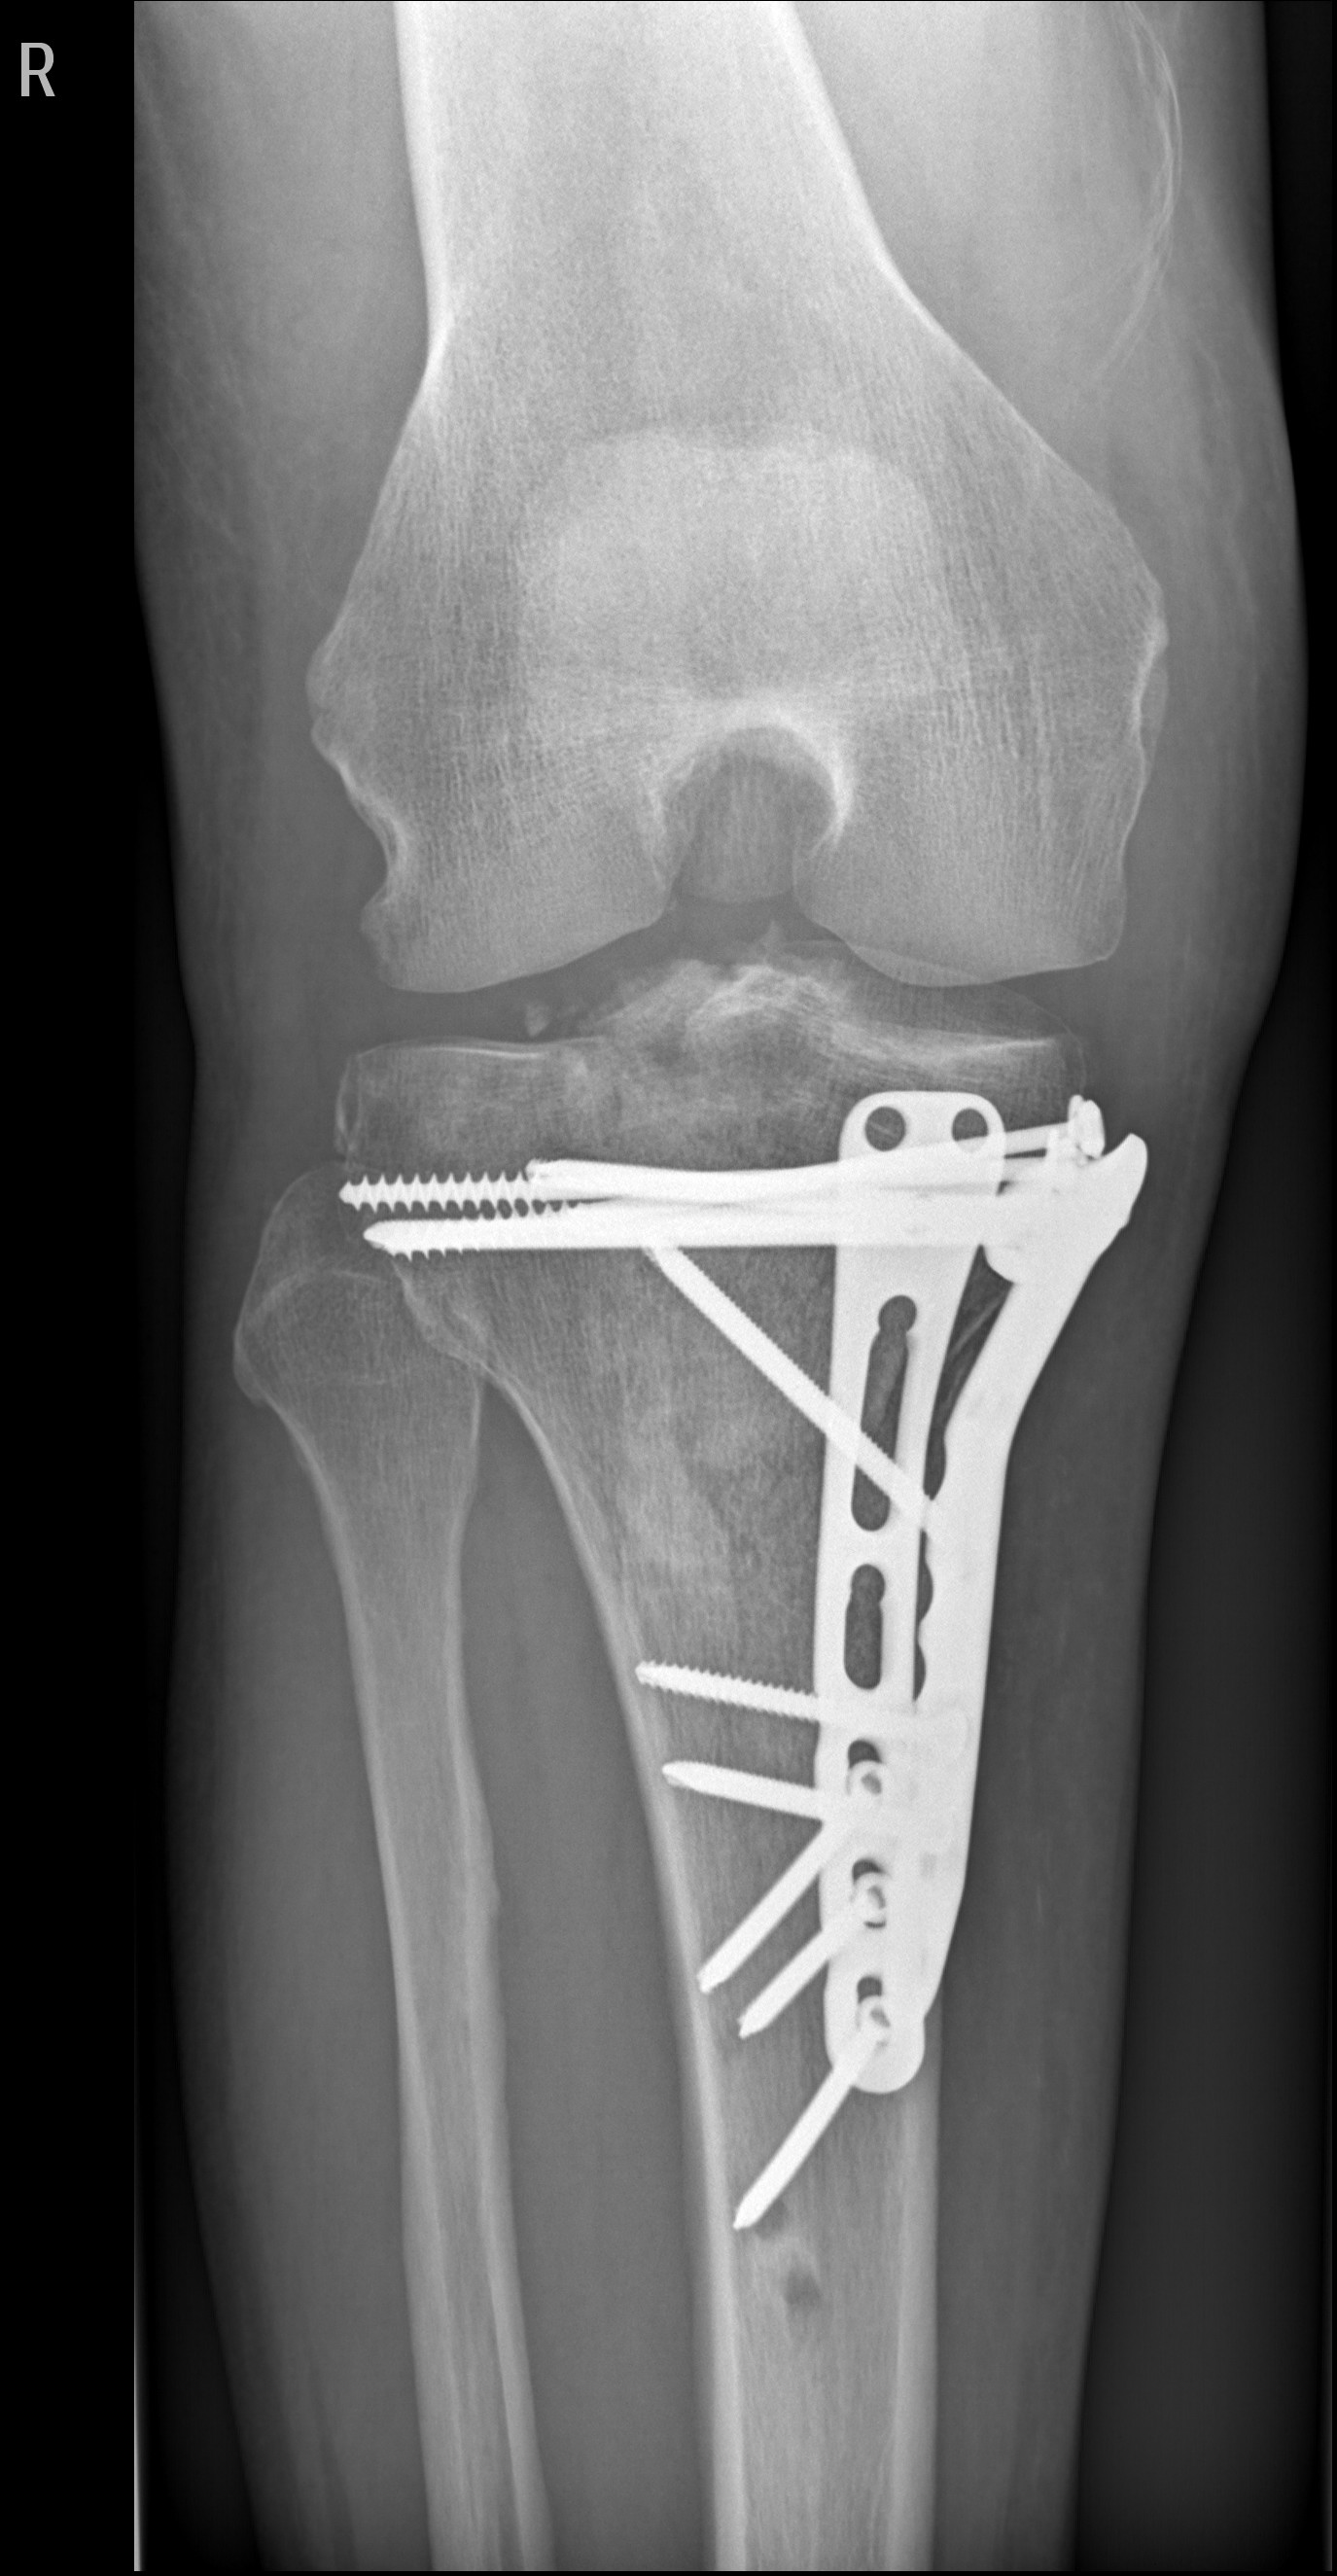

Lange Rede, kurzer Sinn, Schienbein rechts innen durch den Zylinder zerschmettert!

Erstes O.P. Externer Fixateur,

Zweiter O.P.-Bissjen titanium.